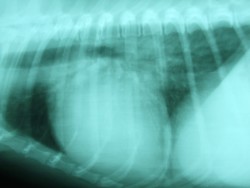

hhh Os exames complementares de cardiologia (ECG; Ecocardiogramas; Raio X torácico permitem detectar precocemente as patologias cardíacas, bem como são de extrema importância nalgumas raças e em animais geriátricos.